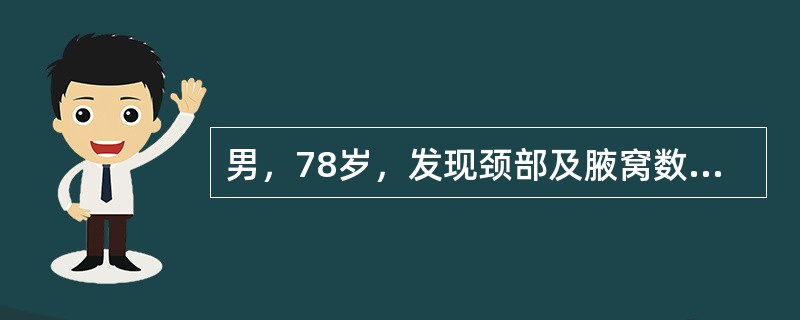

男,78岁,发现颈部及腋窝数个肿大的包块,根据所示图像,最可能的诊断是()

A.肾癌

B.肾转移癌

C.肾淋巴瘤

D.肾上腺癌

E.肾恶性纤维组织细胞瘤